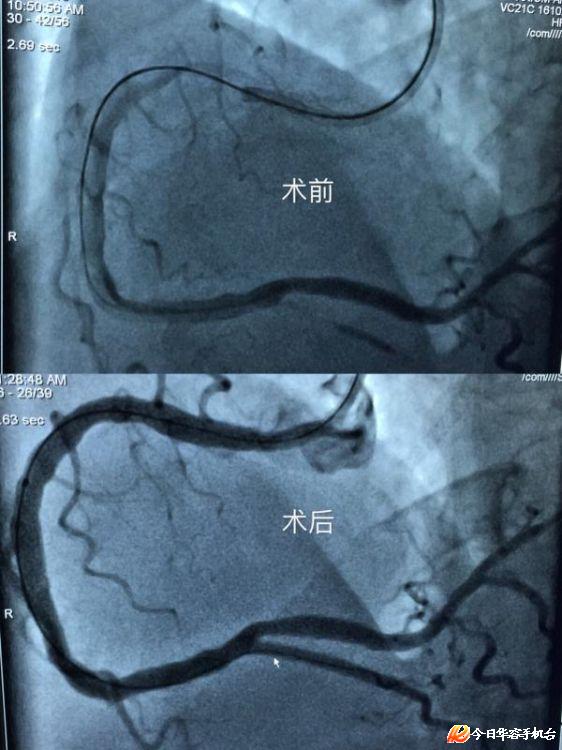

3月20日,华容县人民医院心血管内科成功开展首例复杂冠状动脉慢性完全闭塞病变(CTO)介入手术。此次病例的成功,标志着该院冠状动脉介入治疗能力和水平又进入了一个新的高度。

手术患者因“反复胸闷 、心悸1年”于近期入住县人民医院,3月18检查显示“多支多处严重弥漫性狭窄病变”。县人民医院心血管内科研讨分析后,建议实施冠状动脉慢性完全闭塞病变(CTO)介入手术。3月20日,与家属沟通后,决定为其实施冠状动脉慢性完全闭塞病变(CTO)介入手术。手术中,经多方尝试,成功植入2枚支架,手术成功。

患者目前胸闷、心悸症状已明显改善。